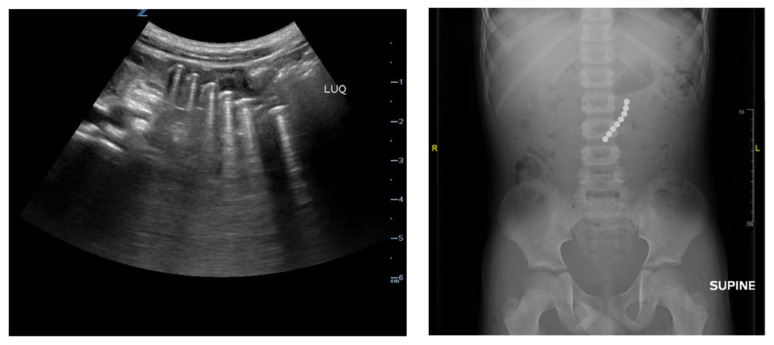

Foreign body ingestions are common complaints in the pediatric emergency department that can be difficult to diagnose in patients with vague symptoms. Magnetic foreign body ingestion can cause significant morbidity and mortality in children. Point-of-care ultrasound (POCUS) is an imaging modality that can be used to readily diagnose emergent abdominal pathology in a timely matter at the patient's bedside. In the case described in the report below, a 6-year-old male swallowed multiple round magnets, causing severe abdominal pain. This was detected on POCUS. An abdominal radiograph also confirmed the POCUS findings of multiple hyperechoic round foreign bodies. Key clinical features and sonographic findings are discussed that may help clinicians using POCUS to identify ingested foreign bodies in Pediatric Emergency Departments.